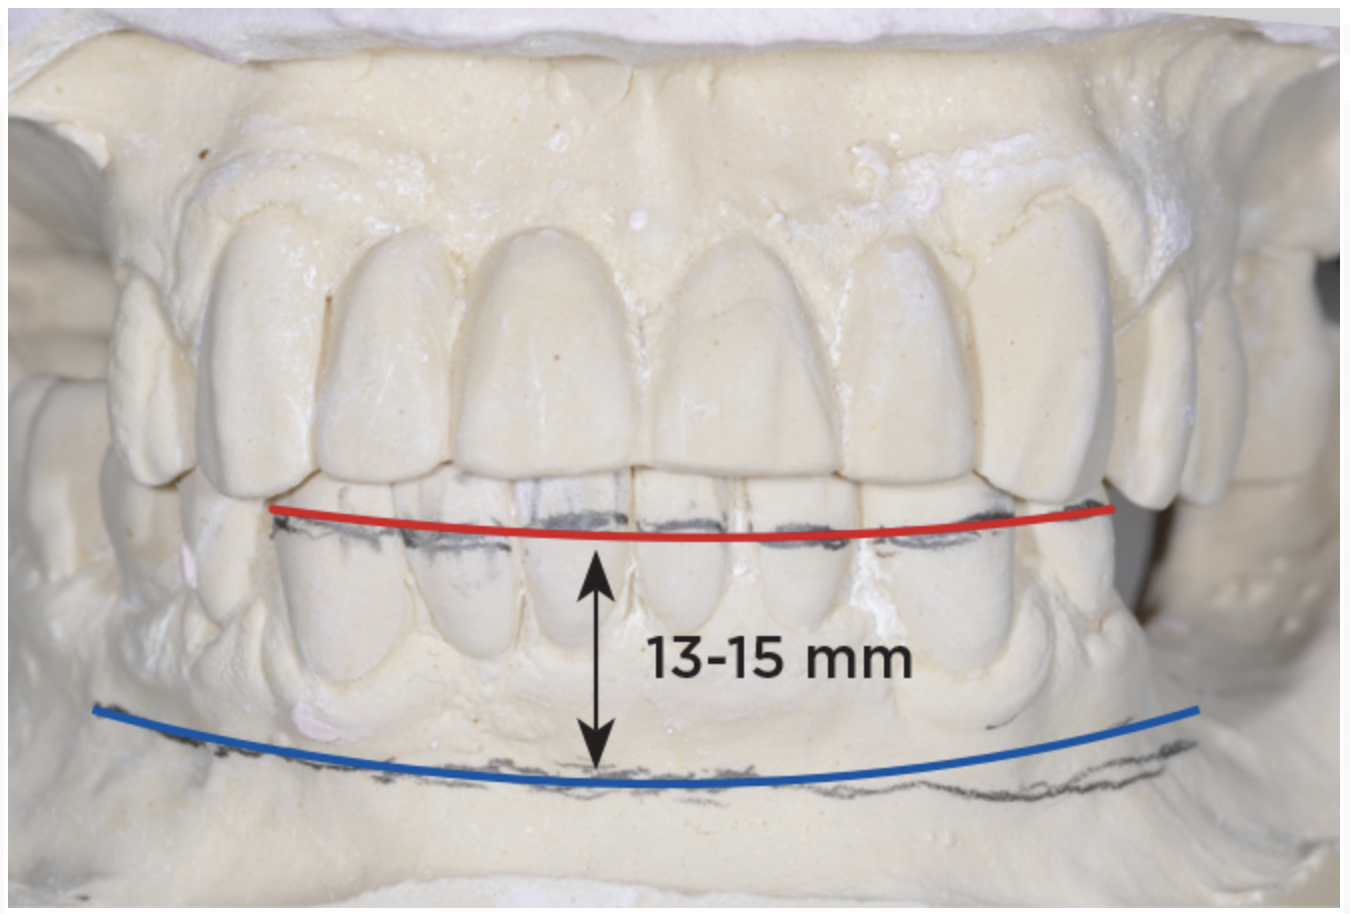

An important advantage of this approach is the ability to simulate bone reduction on the models and verify the presence of 15 mm to 17 mm and 13 mm to 15 mm of required inter-occlusal space for maxillary and mandibular restorations, respectively. This creates a platform for a diagnostic wax-up of the proposed dental rehabilitation and fabrication of wax prosthesis try-ins when necessary. Finally, a modified All-on-4 provisional prosthesis surgical and restorative guide developed by the authors for restoration-driven surgery and simplified restorative procedures is fabricated (Figure 2 through Figure 8).

Fig 3. Desired changes in the incisal plane are marked on the diagnostic models.

Figure 3

Fig 4. Diagnostic wax-up performed after model surgery simulating maxillary tooth extraction. Note that inferior repositioning of the incisal plane helped create the 15 mm to 17 mm inter-occlusal space needed for the maxillary All-on-4 provisional restoration.

Figure 4

Fig 5. Bone reduction model surgery performed in mandibular arch to create 13 mm to 15 mm of inter-occlusal space required for the mandibular All-on-4 provisional restoration.

Figure 5